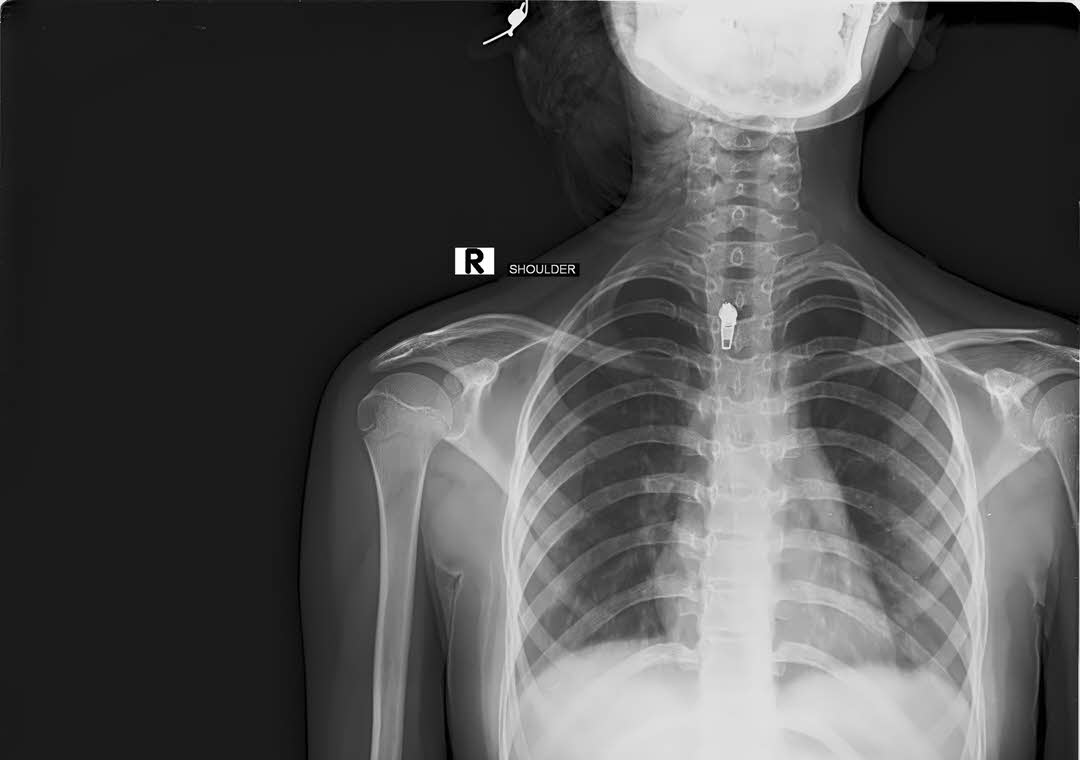

If a foreign object, something that was supposed to be removed during surgery, is left in a patient’s body, that constitutes medical malpractice. There are protocols designed to prevent this from occurring, but this still happens more than it should. The amount of damage caused by that foreign body usually dictates whether or not a malpractice case should be pursued. If you have suffered as a result of a foreign body being left in you, an experienced medical malpractice attorney should be consulted as soon as possible.

Retention of a foreign body after a surgery or other procedure are included in the category of “Never Events” or “Serious Reportable Events (SRE)” These incidents are categorized as such because they should simply never happen. Such a designation means that the consequences are easily avoided by surgeons and other participants in the surgery simply by following established protocols designed to prevent just such medical incidents.